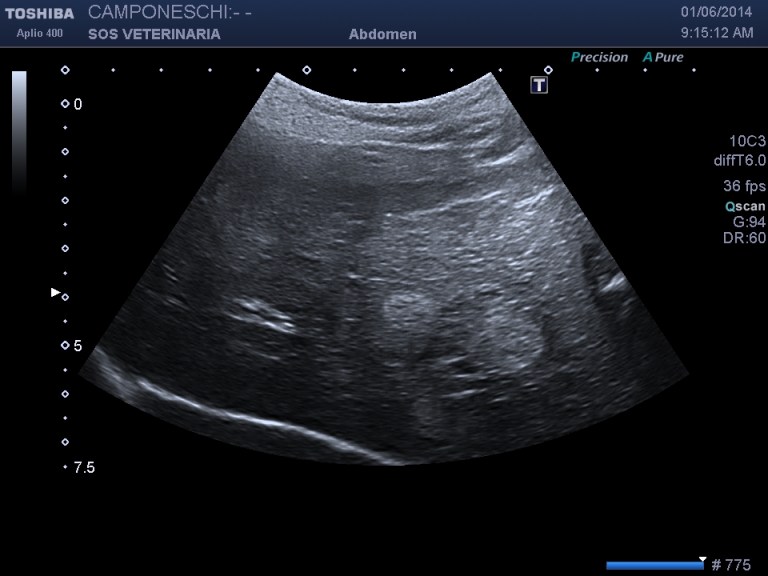

Beagle maschio 13 aa di nome Teo ,insorgenza iperacuta dopo trauma di lieve entita’ (caduta da un muretto alto meno di 1 metro) di sindrome algica addominale acuta ,l’esame ecografico mostra massa irregolare , disomogenea perirenale sx profilo d’organo irregolare e alterato con severa perdita di tessuto corticale ,quadro compatibile con grave infarcimento necrotico- emorragico , eseguito esame ceus ,ha confermato l’avascolarita’ della lesione ,in diagnosi differenziale e’ stato considerato emangiosarcoma renale con rottura secondaria al trauma .

La minima entita’ del trauma ci ha fatto sospettare un emangiosarcoma allo stesso modo di quello splenico in pronto soccorso molto comune alla presentazione . dopo stabilizzazzione di 48 ore e’ stata eseguita nefrectomia .L’esame istopatologico ha escluso un emangiosarcoma e diagnosticato un grave e severo infarcimento necrotico-emorragico con distruzione del 30 % della massa renale ,si ipotizza la rottura di una anomalia presistente forse vascolare per la minima entita’ del trauma che non spiegherebbe se non come eccezione la gravita’ del quadro ..

Un’altra considerazione riguarda la Ceus che in questo caso non ha fornito altre indicazioni se non la conferma di una vasta lesione infartuale emorragica, forse in caso di emangiosarcoma, la presa del contrasto nella corteccia confinante sarebbe stata disomogenea e non netta la demarcazione tra tessuto sano e patologico ,le lesioni epatiche sono state prima dell’intervento campionate in citologia e nonostante fossero ipoenanchment in tutte le fasi sono risultate benigne di natura rigenerativa .